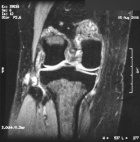

T.Z. - 36 year old woman c/o right anterior and posterior knee pain, swelling for nine months. Persistent, intermittent, sharp pain. Worse with activity. Present at night. Responds to Ibuprofen. No F/C.

PMH: right breast benign cyst

Zoom image: Radiological image Radiological image.